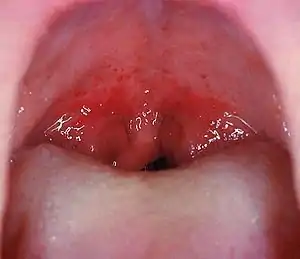

| Red strawberry tongue seen in later stage | |

Strep throat is usually associated with fatigue and a fever of over 39 °C (102.2 °F).[13] The tonsils may appear red and enlarged and are typically covered in exudate.[12] The throat may be red with small red spots on the roof of the mouth.[4] The uvula can look red and swollen.[5] 30% to 60% of cases have associated enlarged and tender lymph nodes in the neck.[5] During the first two days of illness the tongue may have a whitish coating from which red swollen papillae protrude, giving the appearance of a "white strawberry tongue".[5] After four to five days when the white coating sheds it becomes a "red strawberry tongue".[5] The symptomatic appearance of the tongue is part of the rash that is characteristic of scarlet fever.[14][15][16]